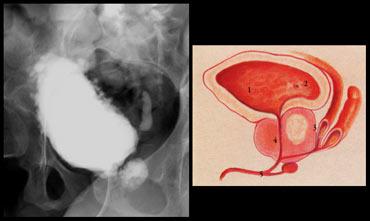

Bên trái là một trẻ bị thoát vị màng não tủy kèm viêm mào tinh hoàn.

Do áp lực bàng quang tăng cao và các cơn co bóp chống lại cơ thắt đóng, đã xảy ra hiện tượng trào ngược không chỉ vào niệu quản trái và tuyến tiền liệt, mà còn vào mào tinh hoàn, dẫn đến viêm mào tinh hoàn.

Trường hợp bên trái cho thấy các đặc điểm điển hình của viêm mào tinh hoàn.

Mào tinh hoàn sưng to và không đồng nhất.

Có tràn dịch màng tinh hoàn và dày thành bìu.

Trên siêu âm Doppler màu cho thấy tăng lưu lượng máu.

Mào tinh hoàn bình thường chỉ có lưu lượng màu hạn chế.